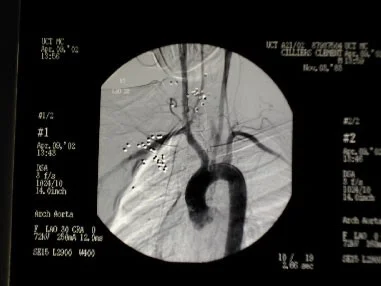

Shotgun pellets 1

Shotgun pellets 2